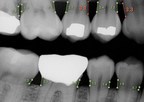

"Overjet's mission is to improve oral health for all," said Dr. Wardah Inam, PhD, co-founder and CEO of Overjet. "Our industry-leading dental artificial intelligence empowers dentists and insurance providers to deliver the best patient care. Overjet's AI software encodes dentist-level understanding of disease identification and progression into precise, bias-free, and repeatable tools for better decision making. We've been thrilled by the fast adoption of AI by the dental community to support consistency, deliver evidence-based care, and improve patient outcomes."

Today's award follows a year of rapid growth for Overjet since the company came out of stealth in 2020 with the launch of powerful dental AI software and financing from VCs that included Crosslink Capital and the MIT-affiliated E14 Fund. Built upon multiple cutting-edge computational dentistry and AI techniques pioneered by Overjet over two years of extensive R&D, Overjet's clinical and claim intelligence platforms are already being used by some of the largest dental customers in the nation.

Overjet is the industry leader in dental artificial intelligence, helping both payers and providers improve patient care. The company was founded by experts from the Massachusetts Institute of Technology and Harvard School of Dental Medicine. Follow us at www.overjet.ai and @overjetdental.